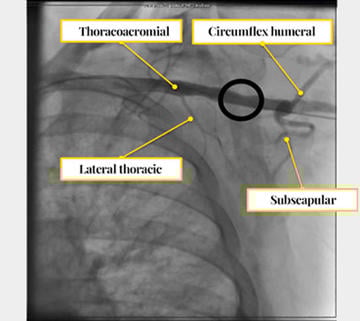

- Prefer left axillary in most cases for a more favorable orientation to the aortic valve; reserve the right axillary artery for cases where the left is unsuitable (Figures 1- 5).

Figure 2: Axillary artery segmentation

Figure 3: Reference collateral arteries